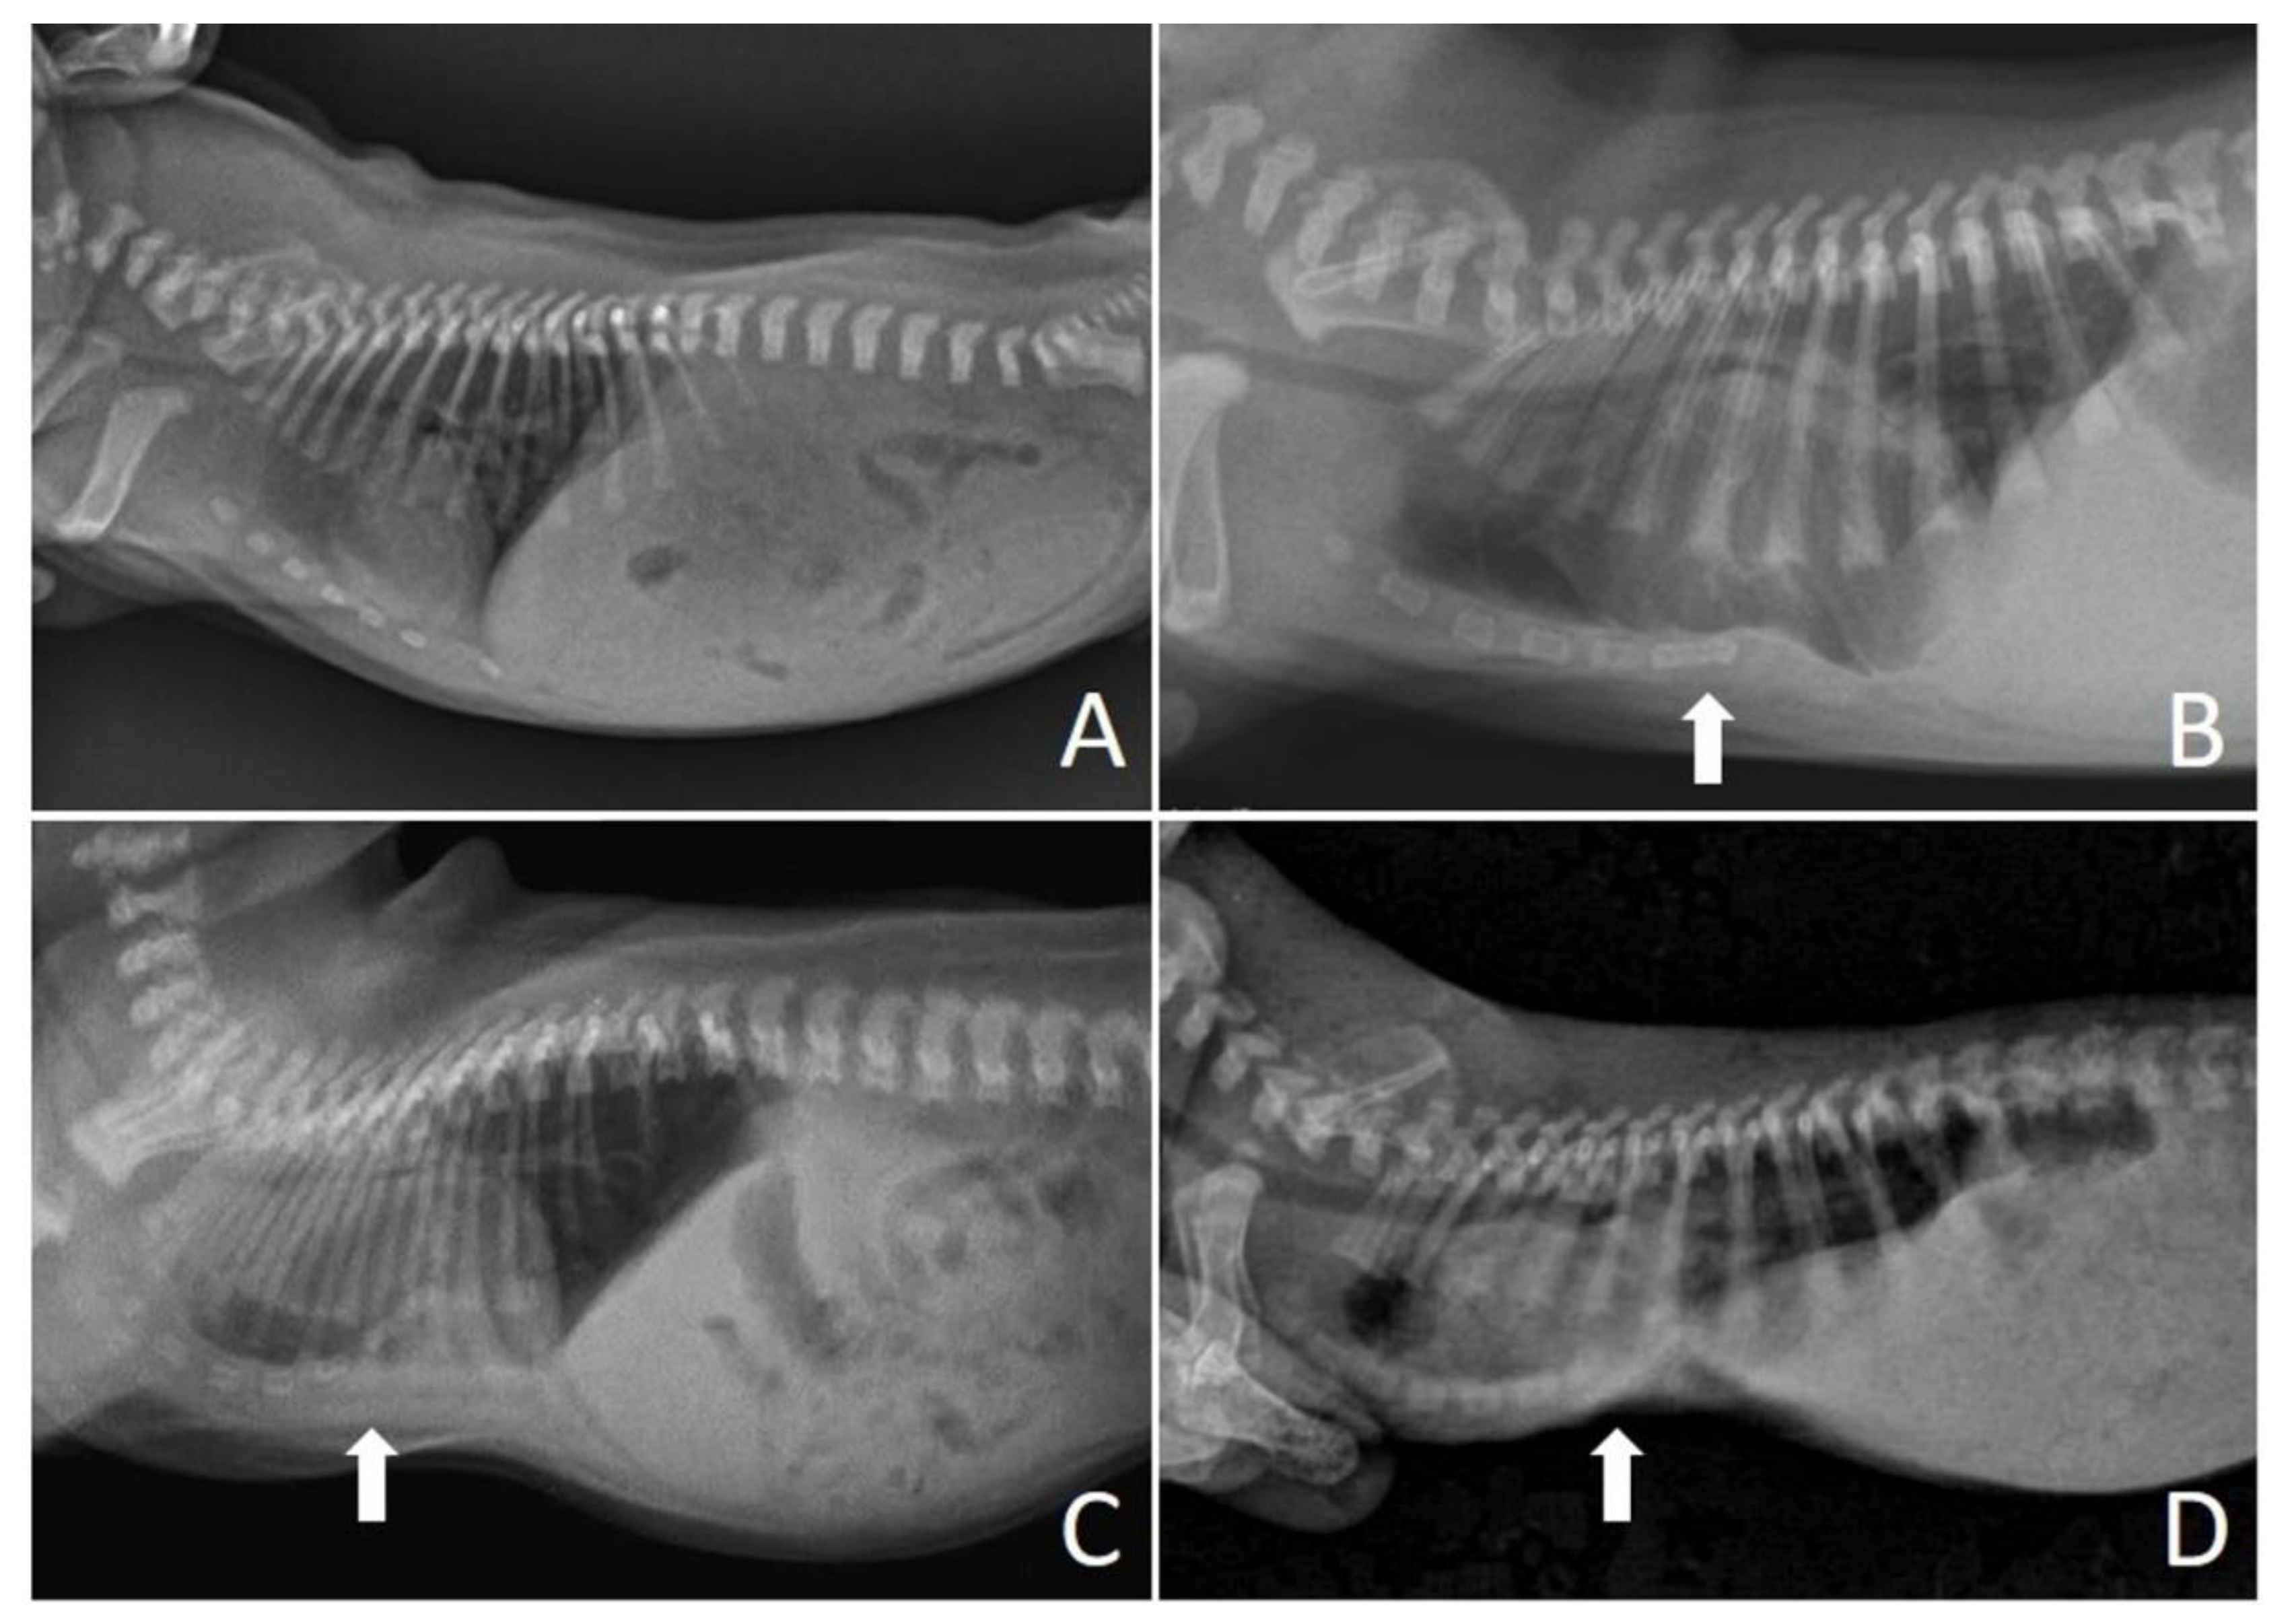

Figure 2.

Chest X-rays of neonatal puppies of brachycephalic breeds. (A) Chest without alterations, indices—frontosagittal: 1.14 cm; vertebral: 13.4 cm. (B) Pectus excavatum of mild degree (arrow), indices—frontosagittal: 2 cm; vertebral: 11.25 cm. (C) Pectus excavatum of moderate degree (arrow), indices—frontosagittal: 3 cm; vertebral: 6 cm. (D) Severe pectus excavatum (arrow), indices—frontosagittal: 3.14 cm; vertebral: 5.8 cm.